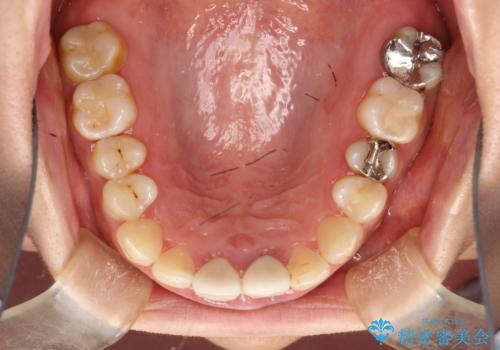

終了時

かなり久しぶりの歯科医院との事で、全体的に古くからの歯垢・歯石が多く付着していたため、自費クリーニング(PMTC)60分コース・歯周ポケット検査(保険適応)を行いました。

磨き残しが放置されると、そこで病原菌が繁殖し始めます。よって歯肉に炎症が生じ、歯周病の原因になることがあります。

定期的に、歯周病検査や専門的なクリーニングをすることで、早期発見につながります。